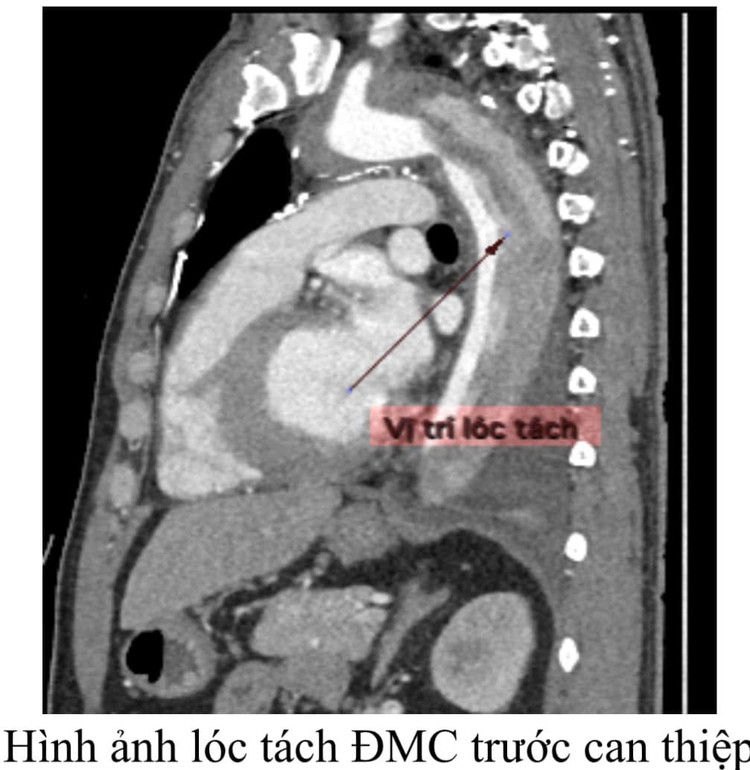

Bệnh nhân H.V.T (47 tuổi), có tiền sử tăng huyết áp không kiểm soát, nhập viện trong tình trạng đau ngực dữ dội. Qua thăm khám, các bác sĩ nhận thấy dấu hiệu huyết áp chênh lệch rõ rệt giữa hai tay (tay phải 200/110 mmHg, tay trái 160/90 mmHg) nghi ngờ lóc tách động mạch chủ ngực.

Ngay lập tức, bệnh nhân được chỉ định chụp MSCT mạch máu, kết quả: lóc tách động mạch chủ ngực cấp tính lan xuống động mạch chủ bụng, nguy cơ vỡ động mạch và tử vong bất cứ lúc nào. Thật không may cho người bệnh vì giải phẫu vị trí lóc tách ngay sát động mạch dưới đòn trái, không đủ vị trí để đặt Stent Graft.